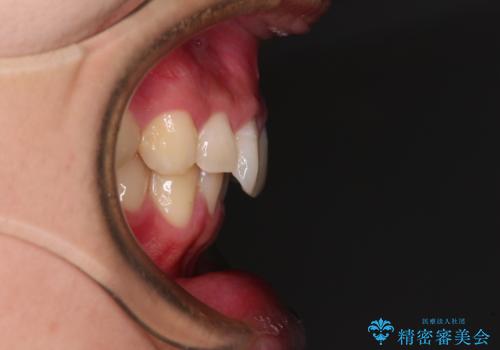

下顎前歯が一本欠損しており、下顎の歯列が小さいため、ディープバイトになりやすい状態でした。

傾斜しいている大臼歯を立ち上げながら、下顎歯列を上顎に対して前方位となるように工夫し、デコボコを解消した上でディープバイトも改善することができました。